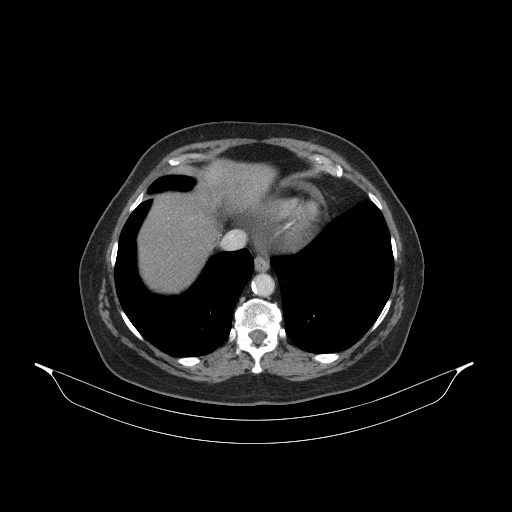

Generated VENOUS CT scan (A→B translation)

Full window (WL 1023.5, WW 4095 β†’ Low βˆ’1024, High +3071)

Actual HU range: [-876.3, 832.7]

Lung window (WL -600, WW 1500 β†’ Low βˆ’1350, High +150)

Actual HU range: [-876.3, 150.0]

Mediastinum window (WL 40, WW 400 β†’ Low βˆ’160, High +240)

Actual HU range: [-160.0, 240.0]